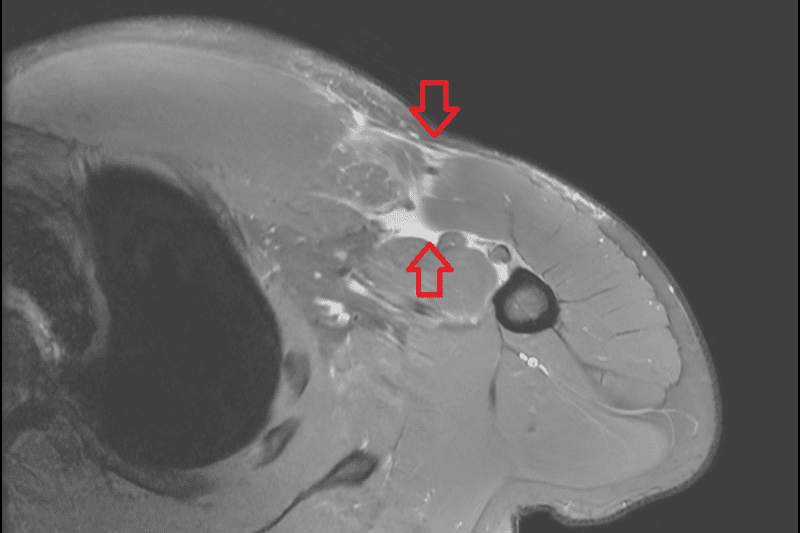

核磁共振檢查發現其右側胸大肌斷裂。

在檢查方面,醫師會先透過病史詢問與理學檢查,觀察胸型輪廓、瘀青分布、肌力變化與肌腱走向,並進一步以核磁共振檢查確認斷裂位置與程度。治療方式則需依病人狀況綜合評估,對於部分撕裂、功能需求不高的病人,可先採取保守治療,如休息、止痛藥物與復健訓練;但若為急性期完全斷裂,手術通常能帶來較佳的力量與外觀恢復。過去治療以傳統經骨縫合手術為主,需要在胸骨上鑽數個孔洞,再將斷裂的肌腱經孔洞縫合至原位。而近年則多採用縫線錨釘或皮質鈕扣等醫材進行固定,利用約4-6公分的手術傷口將斷裂的肌腱以高強度縫線重新拉回並固定在附著位置,不僅固定強度佳,也能減少對骨頭與周邊組織的破壞,有效降低術後疼痛,並幫助病人及早展開復健。李奕澄醫師補充,病人術後需依照醫師指引進行復健,整體而言,胸大肌修復後多數病人可望半年內回到運動或工作,但實際時程仍需視受傷程度與復健遵從性而定。